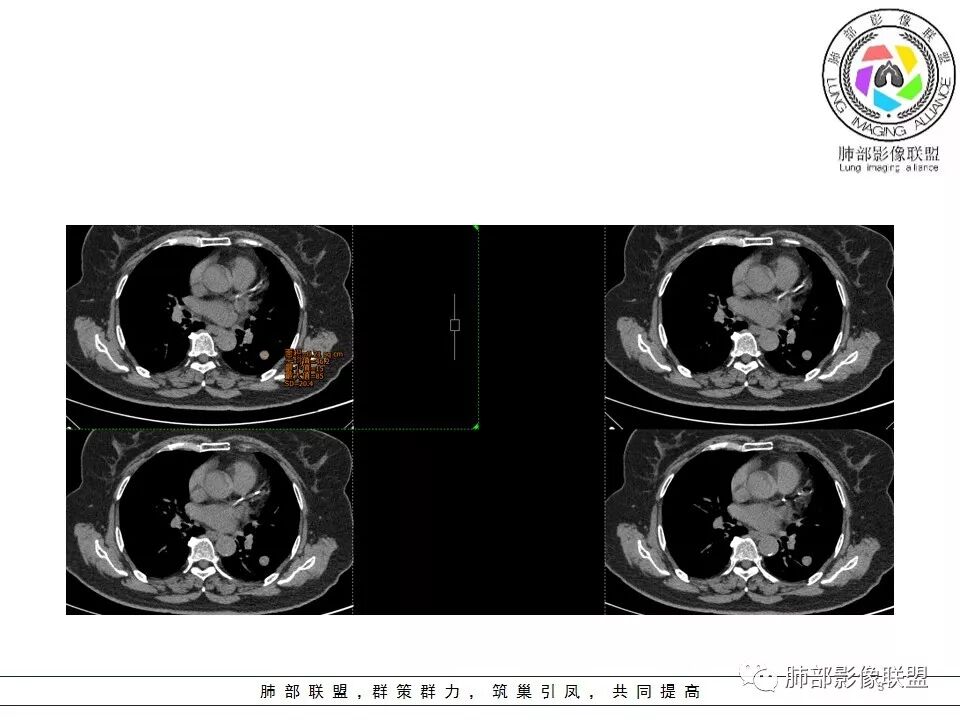

病理结果

错构瘤

临床概述

肺错构瘤(pulmonary hamartoma)系包含肺的所有正常组织成分,致构成成分数量异常、排列异常或分化程度异常等形成的肿瘤样畸形,并非真正的肿瘤。

是最常见的良性肿瘤。一般为单发,多发者极为罕见,约90%发生于肺实质内,10%发生于支气管。在右肺的较左肺多,在下叶的较上叶多,部分发生在右中叶和左上叶舌段。肺错构瘤的来源和发病原因尚不十分清楚,比较容易被接受的假说认为,错构瘤是支气管的一片组织在胚胎发育时期倒转和脱落,被正常肺组织包绕,这一部分组织生长缓慢,也可能在一定时期内不生长,以后逐渐发展才形成瘤。错构瘤大多数在40岁以后发病这个事实支持这一假说。男性发病率为女性的发病率2~4倍,多见于40岁左右,由于肿块位于肺脏周围,患者多无症状,极少咯血。

影像学表现

●直径约1~4cm,有完整包膜,边缘光滑或轻度分叶结节,是最常见的分叶的良性肿瘤;

●可以看到点状、块状、弧形或环形钙化灶;特征性钙化呈爆米花样,但是少见。见到钙化须与结核球鉴别。

●CT上,60%病例可见脂肪密度(CT值-40~-120HU),由于通常含有脂肪、软骨、纤维组织和上皮成分,肿块的CT值离散度大。

●强化方式取决于错构瘤的内部的成份,如果含脂肪及软骨成份较多,血管含量少,血供不丰富,CT增强仅表现为轻度强化或无明显强化;当含平滑肌及腺体成分多时,可出现较明显的强化,但少见。

●错构瘤虽然是良性肿瘤,但有时它也会缓慢生长,逐渐增大,周围血管也会出现推移,所以也会出现“血管贴边征”。

鉴别诊断

边缘光滑的肺结节内出现脂肪组(CT值-40~-120HU),可确诊为错构瘤。当CT上见不到脂肪组织时或病灶太小观察不到,肺错构瘤的诊断难度加大。硬化性肺细胞瘤(PSP)、类癌及转移瘤大多强化显著。与其他孤立性良性肺结节(软骨瘤、结核球等)有时候难以鉴别。